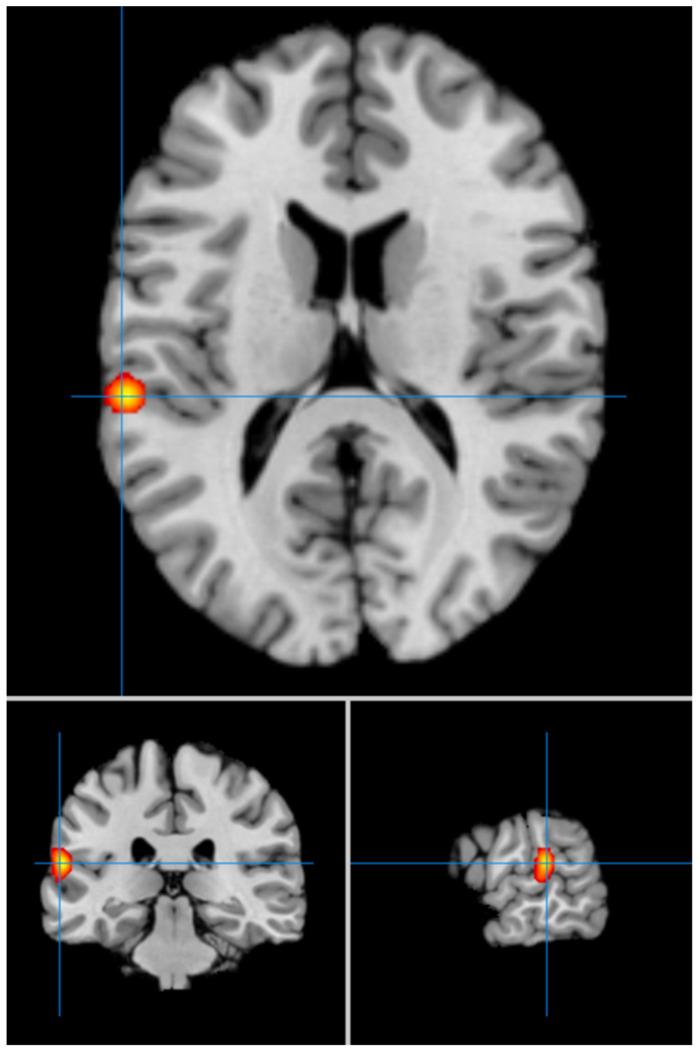

Late-life depression (LLD) is a relatively common and debilitating mental disorder, also associated with cognitive dysfunctions and an increased risk of mortality. Considering the growing elderly population worldwide, LLD is increasingly emerging as a significant public health issue, also due to the rise in direct and indirect costs borne by healthcare systems. Understanding the neuroanatomical and neurofunctional correlates of LLD is crucial for developing more targeted and effective interventions, both from a preventive and therapeutic standpoint. This ALE meta-analysis aims to evaluate the involvement of specific neurofunctional changes in the neurophysiopathology of LLD by analysing functional neuroimaging studies conducted on patients with LLD compared to healthy subjects (HCs). We included 19 studies conducted on 844 subjects, divided into 439 patients with LLD and 405 HCs. Patients with LLD, compared to HCs, showed significant hypoactivation of the right superior and medial frontal gyri (Brodmann areas (Bas) 8, 9), left cingulate cortex (BA 24), left putamen, and left caudate body. The same patients exhibited significant hyperactivation of the left superior temporal gyrus (BA 42), left inferior frontal gyrus (BA 45), right anterior cingulate cortex (BA 24), right cerebellar culmen, and left cerebellar declive. In summary, we found significant changes in activation patterns and brain functioning in areas encompassed in the cortico-limbic-striatal network in LLD. Furthermore, our results suggest a potential role for areas within the cortico-striatal-cerebellar network in the neurophysiopathology of LLD.

老年期抑郁症(LLD)是一种相对常见且使人衰弱的精神障碍,还与认知功能障碍及死亡风险增加有关。鉴于全球老年人口不断增长,LLD日益成为一个重大的公共卫生问题,这也是由于医疗系统承担的直接和间接成本不断上升所致。从预防和治疗的角度来看,了解LLD的神经解剖学和神经功能相关性对于开发更具针对性和有效性的干预措施至关重要。这项激活可能性估计(ALE)元分析旨在通过分析对LLD患者与健康受试者(HCs)进行的功能神经影像学研究,评估特定神经功能变化在LLD神经生理病理学中的作用。我们纳入了对844名受试者进行的19项研究,其中分为439名LLD患者和405名HCs。与HCs相比,LLD患者右侧额上回和额中回(布罗德曼区(BAs)8、9)、左侧扣带回皮质(BA 24)、左侧壳核和左侧尾状核表现出明显的激活不足。同样这些患者左侧颞上回(BA 42)、左侧额下回(BA 45)、右侧前扣带回皮质(BA 24)、右侧小脑山顶和左侧小脑山坡表现出明显的激活过度。总之,我们发现LLD患者皮质-边缘-纹状体网络区域的激活模式和脑功能存在显著变化。此外,我们的结果表明皮质-纹状体-小脑网络内的区域在LLD神经生理病理学中可能发挥作用。